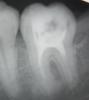

samaia Опубликовано 8 февраля, 2011 Поделиться Опубликовано 8 февраля, 2011 Сегодня лечили зуб, врач сказала, что нужно удалить 3 нерва (зуб крайний нижний справа, извиняюсь, что не знаю его номера). до этого 3 дня ходила с мышьяком. Первый нерв был удален безболезненно, второй был немного "живой", но и его удалили удачно. с третьим возникла проблема - врач очень долго его искала, когда нашла долго не могла поддеть, и как мне показалось, нерв не удалила( при пломбировании канала была просто адская боль, врач сказала, что боль вызвана тем, что она инструментами задевает стенку зуба, а не из-за пульпы. Вечером сделала снимок. Не могли бы вы подсказать - что меня ждет в следующее посещение??? Удален ли нерв??? P.S. пломба стоит временная, постоянную ставить только в следующий вторник...P.P.S. зуб к вечеру разболелся очень сильно (при надкусывании), днем этой боли не было. Врачи сказали, что болит из-за пломбирования каналов, но у меня боль такая, как будто там жив нерв(( Вот снимок Ссылка на комментарий

DokDent Опубликовано 8 февраля, 2011 Поделиться Опубликовано 8 февраля, 2011 Зуб необходимо перелечить.Каналы не пройдены на всю длину,не расширены и,следовательно,недомыты.Поэтому и боли.Если доктор Вас отпустил домой с таким результатом,сомневаюсь,что в следующее посещение он сделает это качественно. Ссылка на комментарий